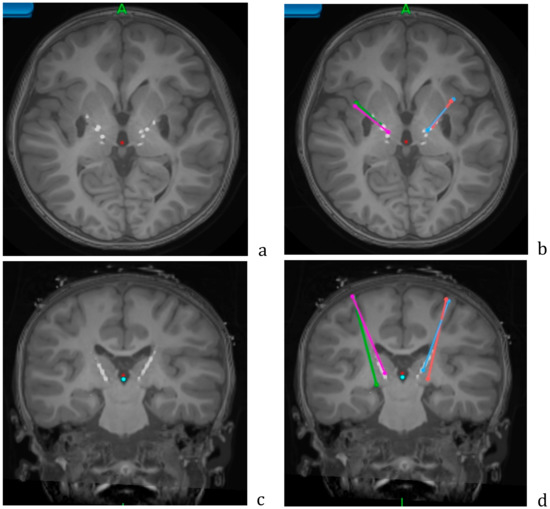

2.6. Second-Phase Surgery

Figure 4. Axial (a,b) and coronal (c,d) views of the postoperative CT overlaid on the preoperative MRI, showing the lead locations for the Adtech stereo EEG leads. Planned trajectories for permanent leads are shown in color (b,d). Data from patient NMU4.